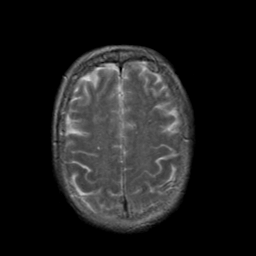

Stroke:T2-weighted MR #2 -- Slice #19

[Home][Help][Clinical] Slice 19